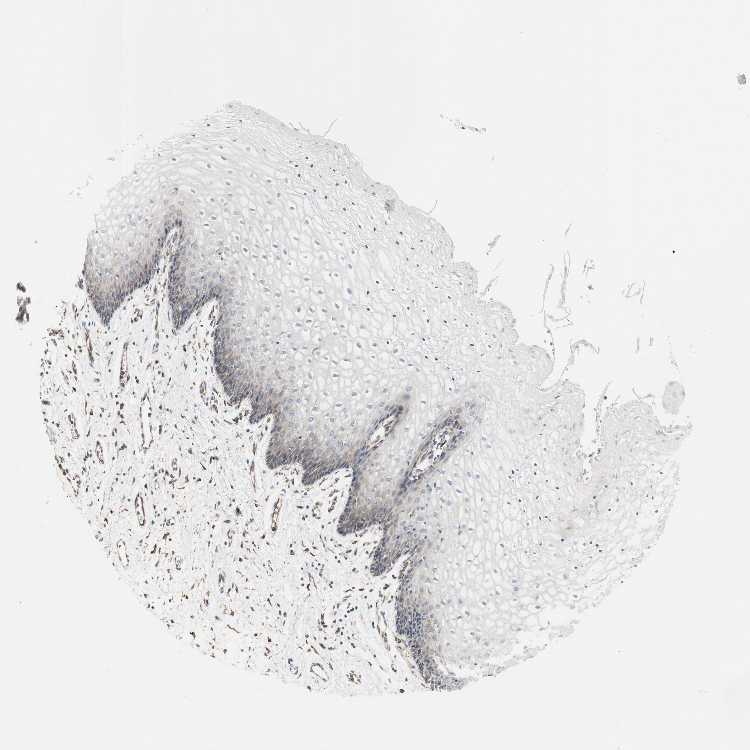

VAGINA - Antibody stainingi

Antibody staining in the annotated cell types in the current human tissue is reported as not detected, low, medium, or high, based on conventional immunohistochemistry profiling in selected tissues. This score is based on the combination of the staining intensity and fraction of stained cells.

Each image is clickable and will lead to virtual microscopy that enables deeper exploration of all samples and also displays staining intensity scores, fraction scores and subcellular localization as well as patient and tissue information for each sample.

Antibody HPA004824Antibody HPA005440

Squamous epithelial cells Not detectedMedium